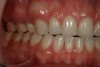

A healthy 24-year-old woman presented to the office with a desire to modify a high, gummy smile and small teeth (Figure 12). Over the course of many years, she had undergone extensive orthodontic treatment, including the removal of four bicuspids. The orthodontic outcome left her arches extremely narrow and her smile line angled severely inward (Figure 13). Clinically, her occlusion was in bilateral group function (Figure 14 and Figure 15). Many dentists with whom she had consulted advised that her only option was to undergo Le Fort I osteotomy to reduce the gumminess of her smile and lessen her vertical maxillary overgrowth (Figure 16). Although this traditional approach may have resolved the issue of her gummy smile, it addressed neither her small teeth as they related to her smile nor her malocclusion. In an effort to provide the patient with a more comprehensive solution, a minimally invasive comprehensive dentistry treatment plan was devised and presented to her. This modern approach would conservatively and effectively address all of the patient’s concerns.